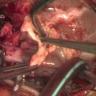

This video shows a teenager with a large neo-aortic root aneurysm and severe aortic valve regurgitation following a Ross procedure, which was treated with a valve-sparing aortic root replacement. The case also highlights the intra-operative management of inadvertent aortic injury during reentry in the setting of severe aortic regurgitation.